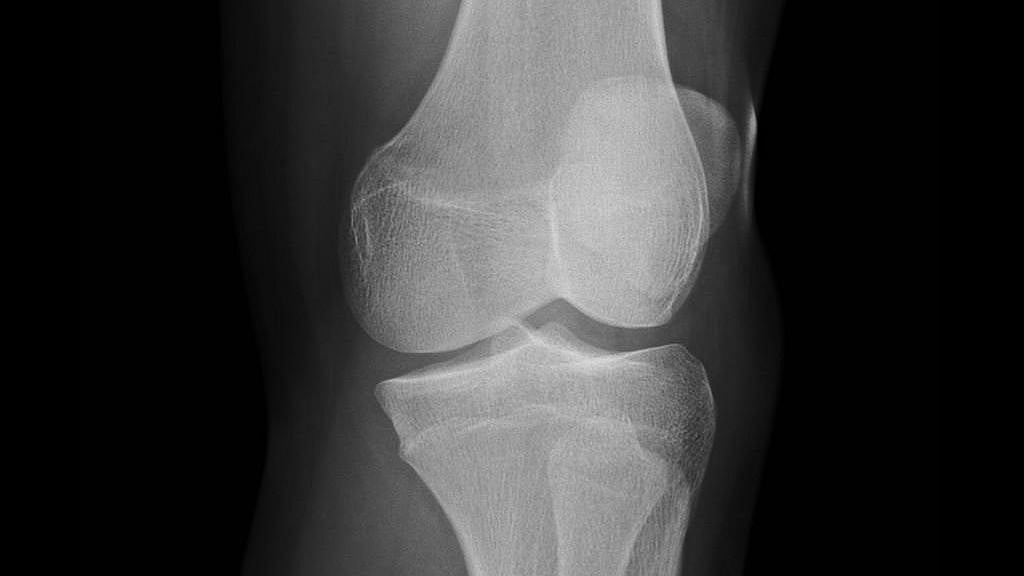

Plain Xray showing Total right knee replacement arthroplasty after Weight Gain After Knee Replacement Surgery the amount of functional gain in obese individuals six months after joint replacement was significant, and similar to that experienced by those. Of 106 adults who had knee replacements,. orthopedic surgeons at mayo clinic modify the risk factors of total knee arthroplasty (tka) or total hip arthroplasty (tha) for a patient with morbid obesity. Find out how to. Weight Gain After Knee Replacement Surgery.